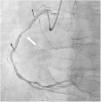

A dobutamine stress echocardiogram was performed, with a clearly positive result, showing development of typical angina, ST elevation in II, III and aVF leads (Figure 3) and motion abnormalities in inferior wall (Video 1). The patient underwent coronary angiography revealing critical stenosis in the middle segment of the right coronary artery (Figure 4), which was successfully treated with stent implantation.